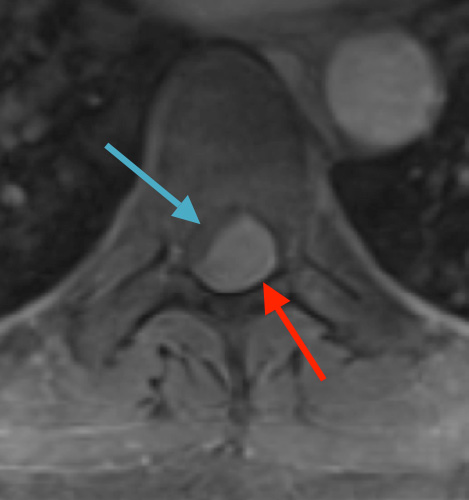

Postoperative MRI T1w demonstrating interval resection with cord re-expansion (blue arrow)

Postoperative MRI T2 illustrating the restoration of CSF surrounding the cord (blue arrow)

Postoperative MRI T1w demonstrating a gross total resection